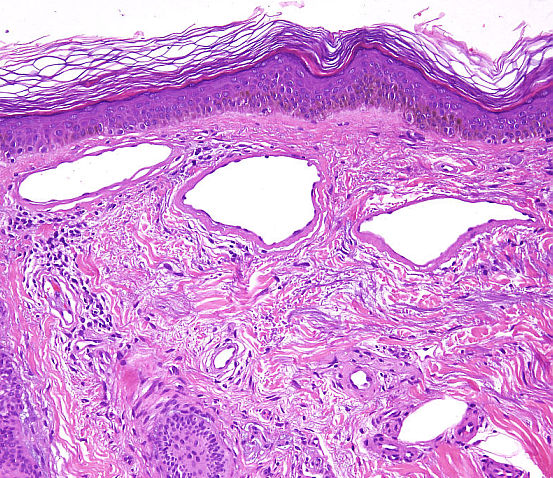

Cas dermatopatologia. Un cas adequat per a aquesta estació de l'any

Gener 2013

Podria suggerir-se el diagnòstic sense conèixer l'historial clínic?